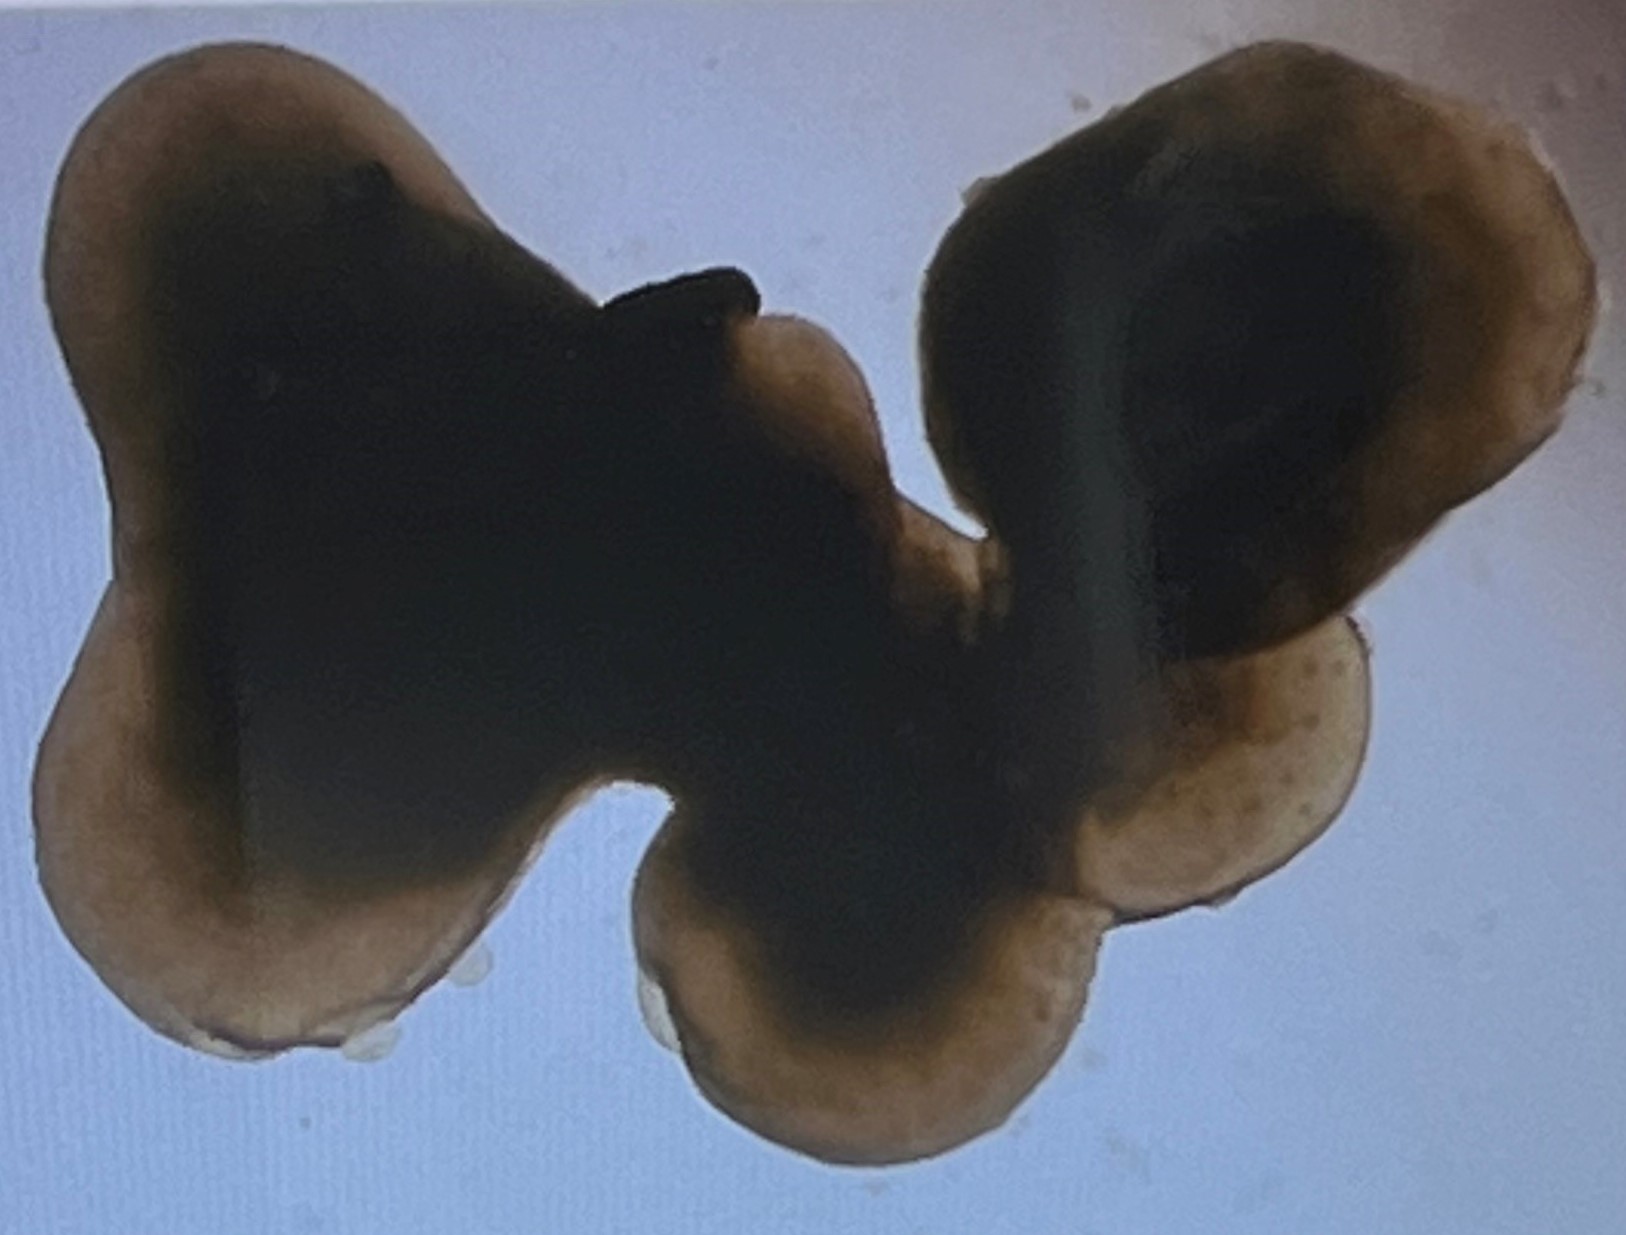

It occurs when the photoreceptors and retinal pigment epithelium (RPE) cells at the macula die over time, causing a gradual, painless but permanent loss of central vision. The macula is the central part of the retina that processes what you see directly in front of you, that is, your central vision. It allows you to achieve high-resolution vision and accounts for your ability to read, recognise faces and to see the world in detail and colour.

Geographic atrophy is a form of advanced age-related macular degeneration (AMD), which primarily affects the macula, which is the part of the retina responsible for sharp, central vision. GA occurs when cells in the macula begin to deteriorate, leading to the gradual loss of vision. This condition can significantly impact daily activities like reading, driving, and recognising faces.